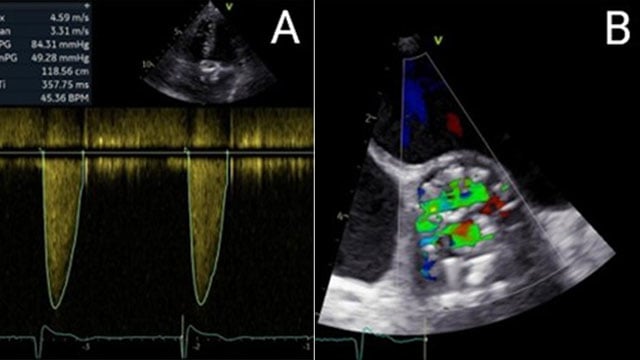

How should I treat a torrential tricuspid valve regurgitation in a young patient who remains symptomatic despite optimal medical therapy?

How should I treat a torrential TR in a young patient who remains symptomatic despite OMT?

A frail patient presents with worsening NYHA class III dyspnoea and peripheral oedema despite optimal medical therapy...